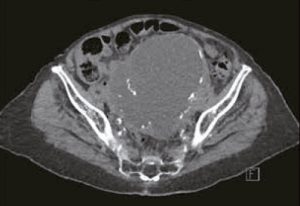

Qui est éligible aux traitements oncologiques après l’âge de 80 ans ? Entre considérations oncogériatriques et éthiques